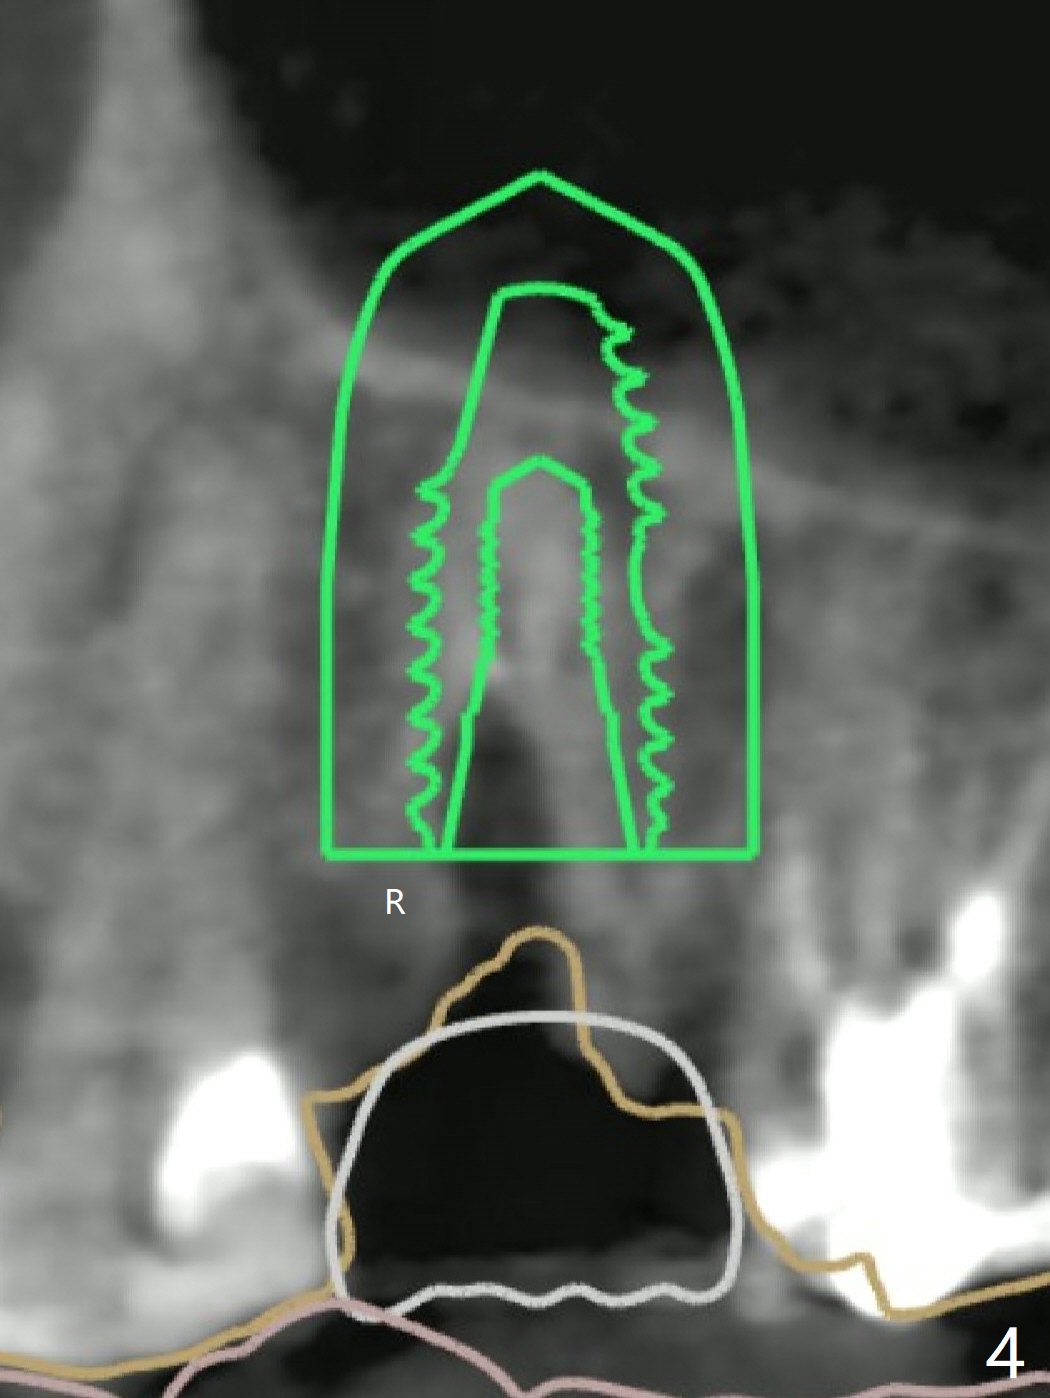

A 49-year-old woman has loose splinted crowns between #13 and 14. After removal of the crowns, the tooth #13 is found non-salvageable (Fig.1). A 4 or 4.5 x 8.5 or 10 mm implant should be able to achieve primary stability because of engagement of the implant into the mesial and distal walls of the socket and the sinus floor. Splinted provisional should provide with additional retention. There is no much need for socket shield, since there is no mesial or distal crestal bone loss (associated with food impaction). If the crown is short, there is no concern about buccal gingival recession. In fact the mesial papilla is more apical than the distal one (Fig.2 *), corresponding to the more apical crest (Fig.3 *). To prevent further mesial crestal loss post extraction, socket shield seems necessary. There appears that the implant is placed distal enough so that a small portion of the mesial root (Fig.4,5 R) is able to be saved. Fig.6 is the occlusal view of the residual root of the tooth #13. The mesial sheath will be kept (Fig.7,8, as compared to Fig.3).